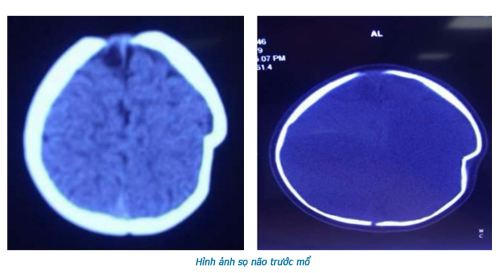

Mới đây, tại Bệnh viện Đa khoa tỉnh Phú Thọ đã tiếp nhận trường hợp bé gái 8 tháng tuổi bị lún sọ não do ngã xe tập đi.